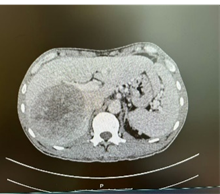

新辅助(两次HAIC和两个周期靶免治疗)后CT

由于病人一般情况较好,肝功能良好(Child-pugh A级),经多学科会诊临床确认肿瘤为IIb期肝细胞癌,属于可切除性肝癌,但存在高危复发因素,建议先行新辅助治疗后手术切除。经两次肝动脉关注化疗(HAIC)(奥沙利铂+5-Fu+亚叶酸钙方案)和两个周期的靶向免疫治疗(仑伐替尼+帕博利珠单抗方案),第二次介入造影是肿瘤血供不明显,第二次介入治疗4周后复查CT提示肿瘤缩小不明显但坏死征象明显,经MRI证实仍有少许血供,于是经多学科会诊后决定行前入路右半肝切除术。